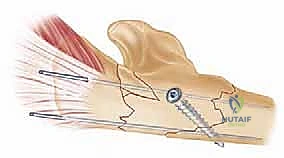

No Articular Involvement of the Ulnohumeral Joint

For ulna fractures distal to the coronoid, where the articular surface of the olecranon or coronoid is not involved:

- Reduction: The primary goal here is to restore ulnar length, axial alignment, and rotation. Apply longitudinal traction to the forearm to disengage fragments. Use reduction clamps (e.g., Verbrugge, pointed reduction clamps) to achieve anatomic reduction of the fracture fragments.

- Pearl: Once the ulna is anatomically reduced and stable, the radial head should spontaneously reduce and remain concentric with the capitellum. This is the "Monteggia rule" in action. If the radial head remains dislocated after a perfect ulnar reduction, suspect soft tissue interposition or a concomitant ligamentous injury requiring further exploration.

- Provisional Fixation: Secure the reduced fragments with K-wires.

- Plate Application: We will use a dorsal plate for definitive fixation.

- Plate Choice: Choose a pre-contoured locking plate or a conventional small fragment plate (e.g., 3.5mm LCP). The plate should be long enough to achieve adequate working length, typically 6-8 cortices proximal and distal to the fracture.

- Plate Placement: The dorsal aspect of the ulna provides a strong tension band effect. Proximally, the plate needs to oppose the olecranon. This often requires a partial split of the triceps tendon longitudinally along its fibers to expose the dorsal surface of the olecranon and allow the plate to sit flush.

- Alternative: Some surgeons prefer lateral plate placement to prevent hardware prominence, but the dorsal aspect is biomechanically superior for most ulnar shaft fractures.

- Screw Insertion:

- Lag Screws: If possible, insert lag screws through the plate or independently across oblique fracture lines to achieve interfragmentary compression.

- Cortical/Locking Screws: Fill the remaining plate holes with cortical or locking screws, ensuring bicortical purchase.

- Fluoroscopic Confirmation: Take AP and lateral fluoroscopic images to confirm anatomic reduction of the ulna, concentric reduction of the radial head, and optimal hardware placement.